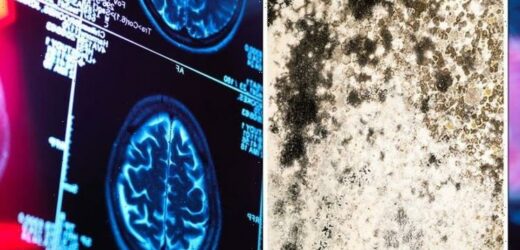

The MRI scan revealed a mysterious O-shaped anomaly on Mr Bottenus’ brain.

After eight months of testing with MRI’s, biopsies, and even spinal taps, his doctors discovered the terrifying origin of his issues: an abscess of black mould growing on his brain.